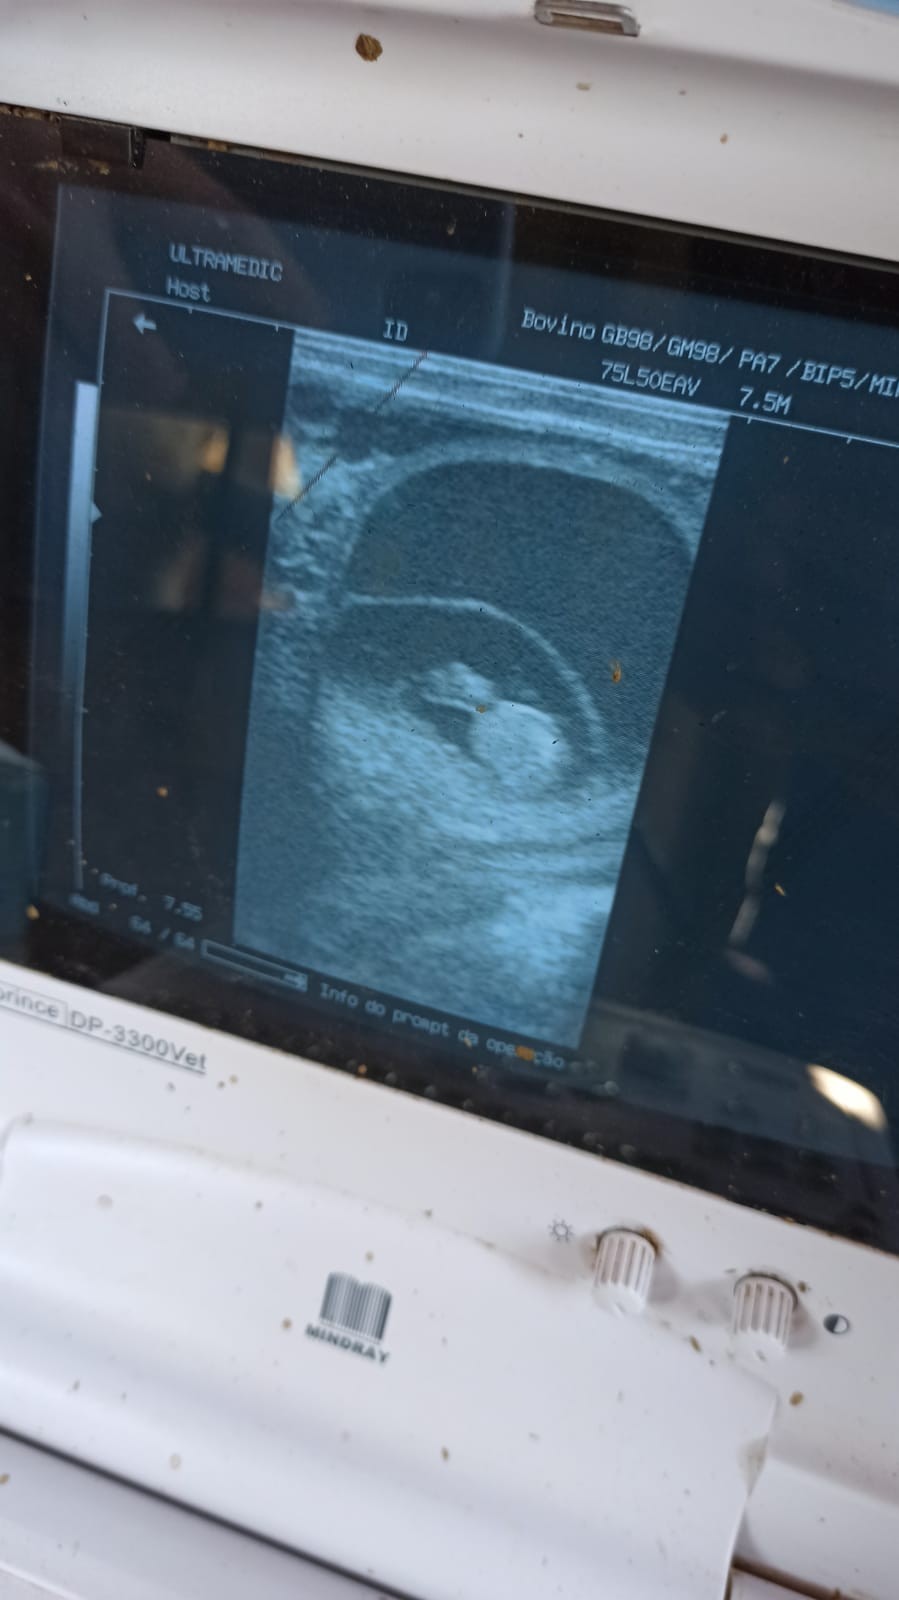

No dia 05 de maio, os alunos do 9º período do curso de Medicina Veterinária do UNICERP junto com o professor Dr. Gustavo Lima, docente da matéria de Clínica Integrada e Clínica de Grandes Animais confirmaram a primeira gestação diagnosticada por meio palpação retal e ultrassonografia realizada nas novilhas da Fazenda Experimental da Instituição. As mesmas foram protocoladas por meio de IATF( Inseminação Artificial em Tempo Fixo) e posteriormente inseminadas pelos alunos, que após 40 dias puderam realizar o procedimento e confirmação da gestação. Tais procedimentos são de suma importância para o desenvolvimento do conhecimento, aperfeiçoamento das práticas e manejos adotados na rotina da Bovinocultura de Leite.